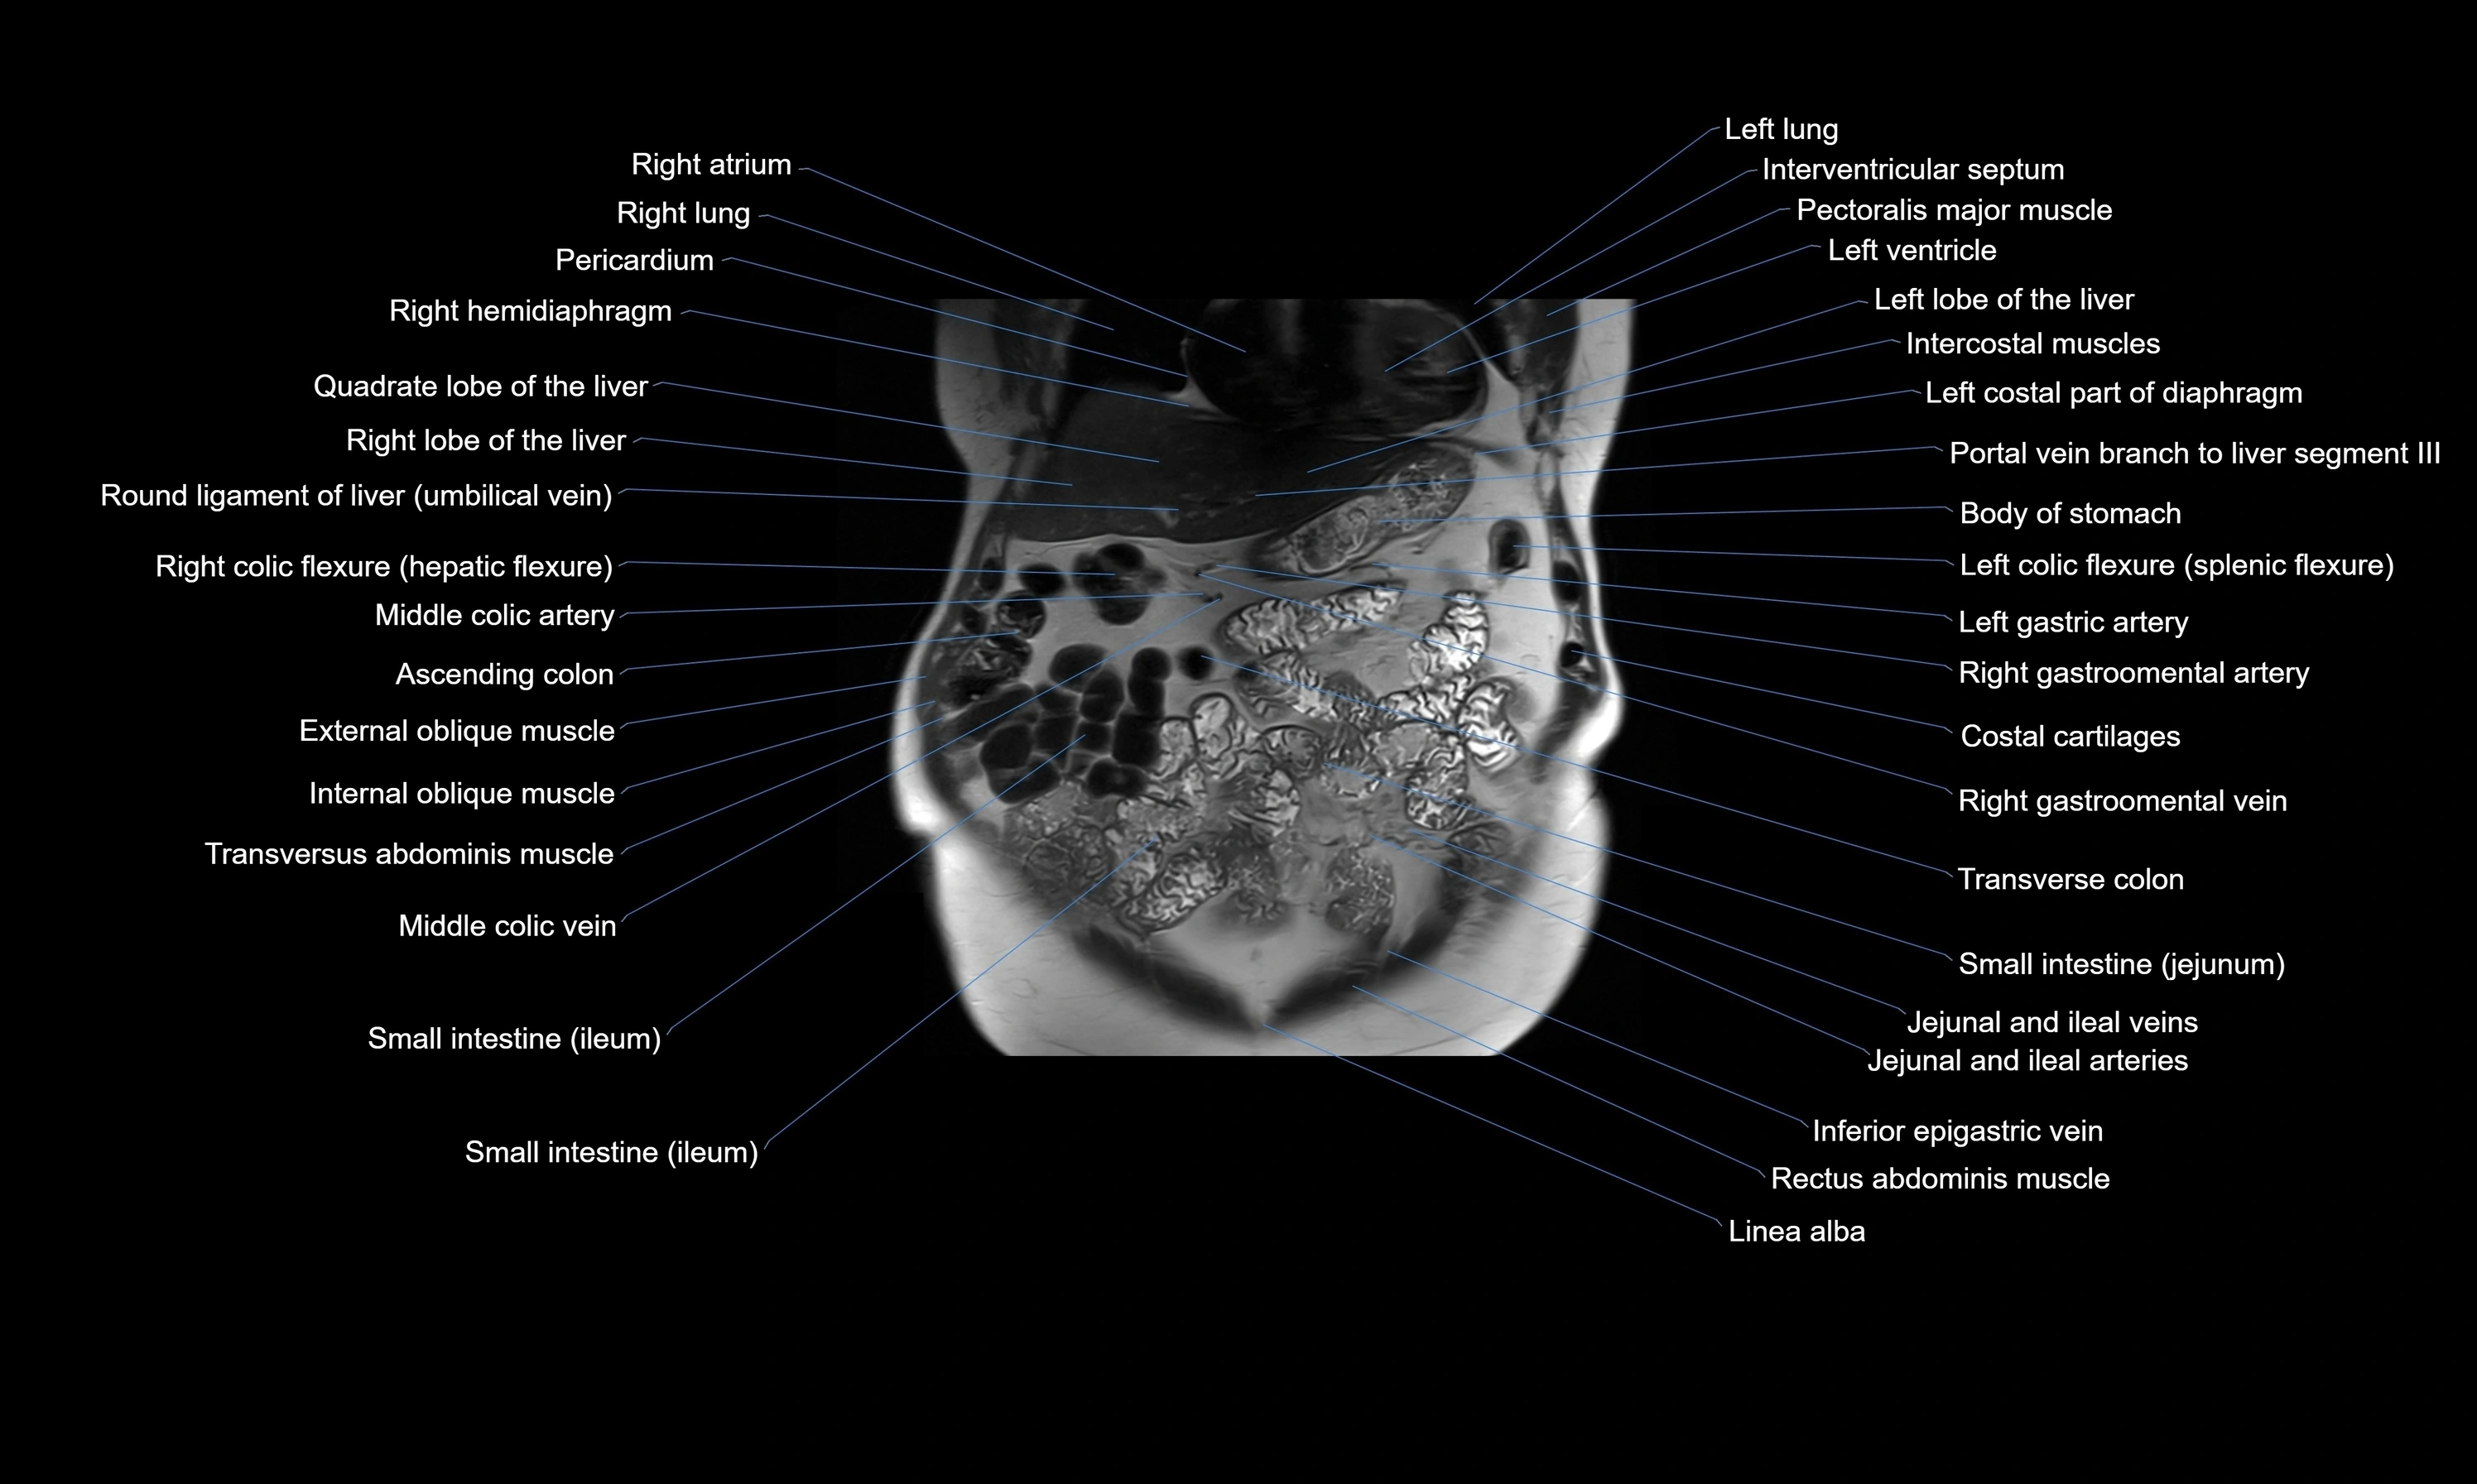

MRI images